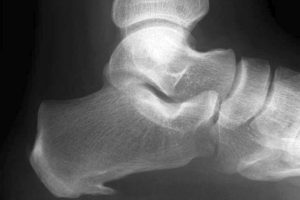

Fitness – Fersensporn behandeln

Von J. Lengerke – Praxis Dr.Jochen Lengerke, CC BY-SA 3.0 de, https://commons.wikimedia.org/w/index.php?curid=20139990 Kommentar: Hi,   wer aktiv durchs Leben geht, kann schon einmal ein Fersensporn-Problem bekommen.   Dabei …